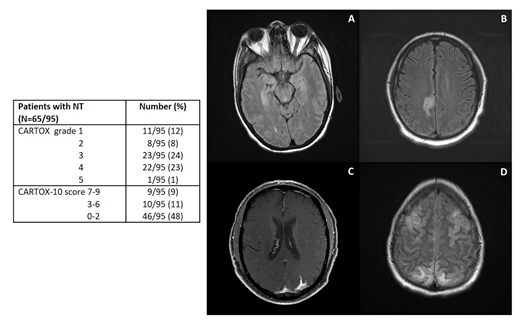

Among the 65 pts who developed NT, a CT head without contrast was performed in 48, and was not evaluable in 2 because of motion artifacts. Among the 46 evaluable scans, 1 (4%) was abnormal as compared to baseline, and showed new onset cortical edema (non-diffuse but symmetrical). An MRI brain with contrast was performed in 36 pts, but was not evaluable in 10 because of lack of baseline, motion artifacts or differences in imaging sequences. Among the 26 evaluable scans, 15 (58%) showed abnormal findings, including autoimmune encephalitis-like, characterized by symmetric white matter changes of the pons and hippocampus (6; Fig. A), stroke-like (4; Fig. B), LMD-like (3; Fig. C) and PRES-like (2; Fig. D), with concomitant cortical edema in 5. EEGs were performed in 52 pts (>1/pt, for a total of 116 EEGs) and were abnormal in 47 (90%). Focal and/or diffuse slowing was the most common abnormality (isolated finding in 35 [73%] pts), while epileptiform discharges and/or non-convulsive status epilepticus (NCSE) were observed 12 (27%) pts. A lumbar puncture was performed in 12 pts: median white blood cell count was 2 cells/µL (range, 0-6), median protein 47 mg/dL (range, 13-600), median glucose 69 mg/dL (range, 30-111), and cytology was positive for malignant cells in 2 (7%) pts. Convulsive seizure was observed in 4 (6%) pts and 10 (15%) received additional anti-seizure therapy for convulsive or non-convulsive seizures. Among the 65 pts with NT, dexamethasone up to 20 mg IV Q6H was given to 42 (65%) pts, methylprednisolone 1000 mg IV daily to 12 (18%), and tocilizumab to 64 (98%; during CRS or CRS with concurrent NT).

Conclusions. Our results suggest that multiple radiological patterns of NT after axi-cel are possible in r/r LBCL pts, MRI being more sensitive than CT scan for their detection. NCSE is a common event, supporting the use of seizure prophylaxis and EEGs for evaluation of these pts. Pts with NT experience a worse outcome, and additional clinical and biological predictors of NT will be analyzed and presented at the meeting.